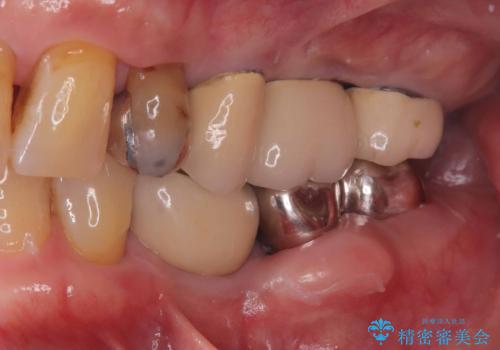

1Dayインプラントは低侵襲なので痛みもほとんどありません。従来のインプラント治療だと1年弱かかるのが、3ヵ月で治療を終える事が出来ました。

術後痛みも無く、3ヵ月で治療を終える事が出来ました。